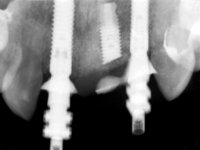

In the initial phase, it was proposed to the patient to perform the surgical implant exposure and after clinical evaluation, make prosthetic decisions. Once the healing screw was placed and the soft tissues were healed, an inadequate position of the implant was found. In view of the dramatic situation, the patient was proposed to remove the implant and put a new one after tissue regeneration. This proposal was rejected by the patient, who suggested temporary rehabilitation of the current implant. A new proposal was then made, to rehabilitate the implant, consisting of a screwed abutment, and on this, the placement of an acrylic crown with coronal and gingival components. After 6 years with the provisional treatment, the patient appeared in consultation with an abscess in tooth 1.1. After clinical and imaging analysis, it was decided to remove teeth 1.1 and 2.2, submerge the implant, place two implants at the site of 1.1 and 2.2 and perform adequate tissue regeneration. Temporization would be done with a provisional 3-element bridge, adhered with a net to the neighboring teeth. After osseointegration, definitive rehabilitation would be done with a 3-element bridge, including zirconia infrastructure and ceramic cover.

The surgical implant exposure and the healing screw placement proved to be a negative surprise regarding its position. Since the proposed removal of the implant was refused, we advanced to its provisional rehabilitation. An open tray impression technique was done, and a screwed abutment with a coronal and gingival component and an acrylic crown were made in the laboratory, using these two components. The provisional crown was placed in the mouth until a final decision was made. Six years passed before the patient returned to the clinic with an abscess on tooth 1.1. The choice to remove teeth 1.1 and 2.2 was made, to create a provisional 3-element bridge with a net to be adhered to the adjacent teeth. Surgery was planned and performed, placing the two implants at the site of 1.1 and 2.2, and the implant at the 2.1 site was cut with the objective of submerging it, while adequate tissue regeneration was performed (Surgical Work performed By Dr. Manuel Neves). During osseointegration, the patient used the fixed provisional bridge. A first impression was made for confection of a zirconia screwed provisional bridge, which worked the soft tissues for twelve weeks. The definitive impression was made with the individualisation of custom impression copings. Final rehabilitation was done with ceramized abutments, and also a bridge with zirconia infrastructure and ceramic cover. Due to the inclination of the implant placed at the site of tooth 1.1, the bridge required cemented fixation.